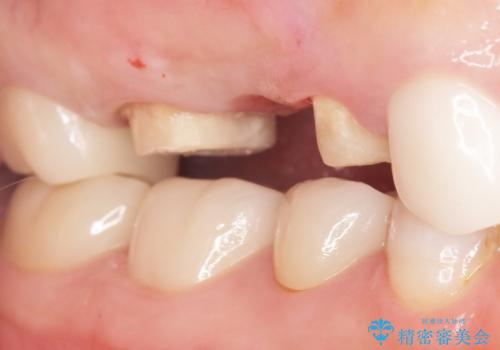

かぶせものと歯ぐきの境目が黒い 40代女性

- 被せ物と歯ぐきの境目が黒いことを気にされ、来院された患者様です。

精査したところ、メタルボンドクラウンの金属部分が露出し黒く見えていました。

患者様のご希望により、金属を使わないオールセラミックのブリッジによる補綴治療を行いました。